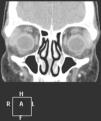

Se solicitó resonancia magnética cerebral, en la que se objetivó un aumento del tamaño de la glándula lagrimal derecha, con afectación supraciliar y orbitolateral superior del ojo derecho, compatible con dacriocistitis / proceso infiltrativo (fig. 1, corte coronal), por lo que es diagnosticada de pseudotumor orbitario con afectación muscular y dacriocistitis, iniciándose corticoterapia a altas dosis y antibioterapia intravenosa, dada la gravedad del proceso. Se realiza una biopsia de la zona inflamada, pero el resultado no es significativo e ingresa para control de la evolución y respuesta a la medicación pautada, dada la gravedad de la afectación ocular.